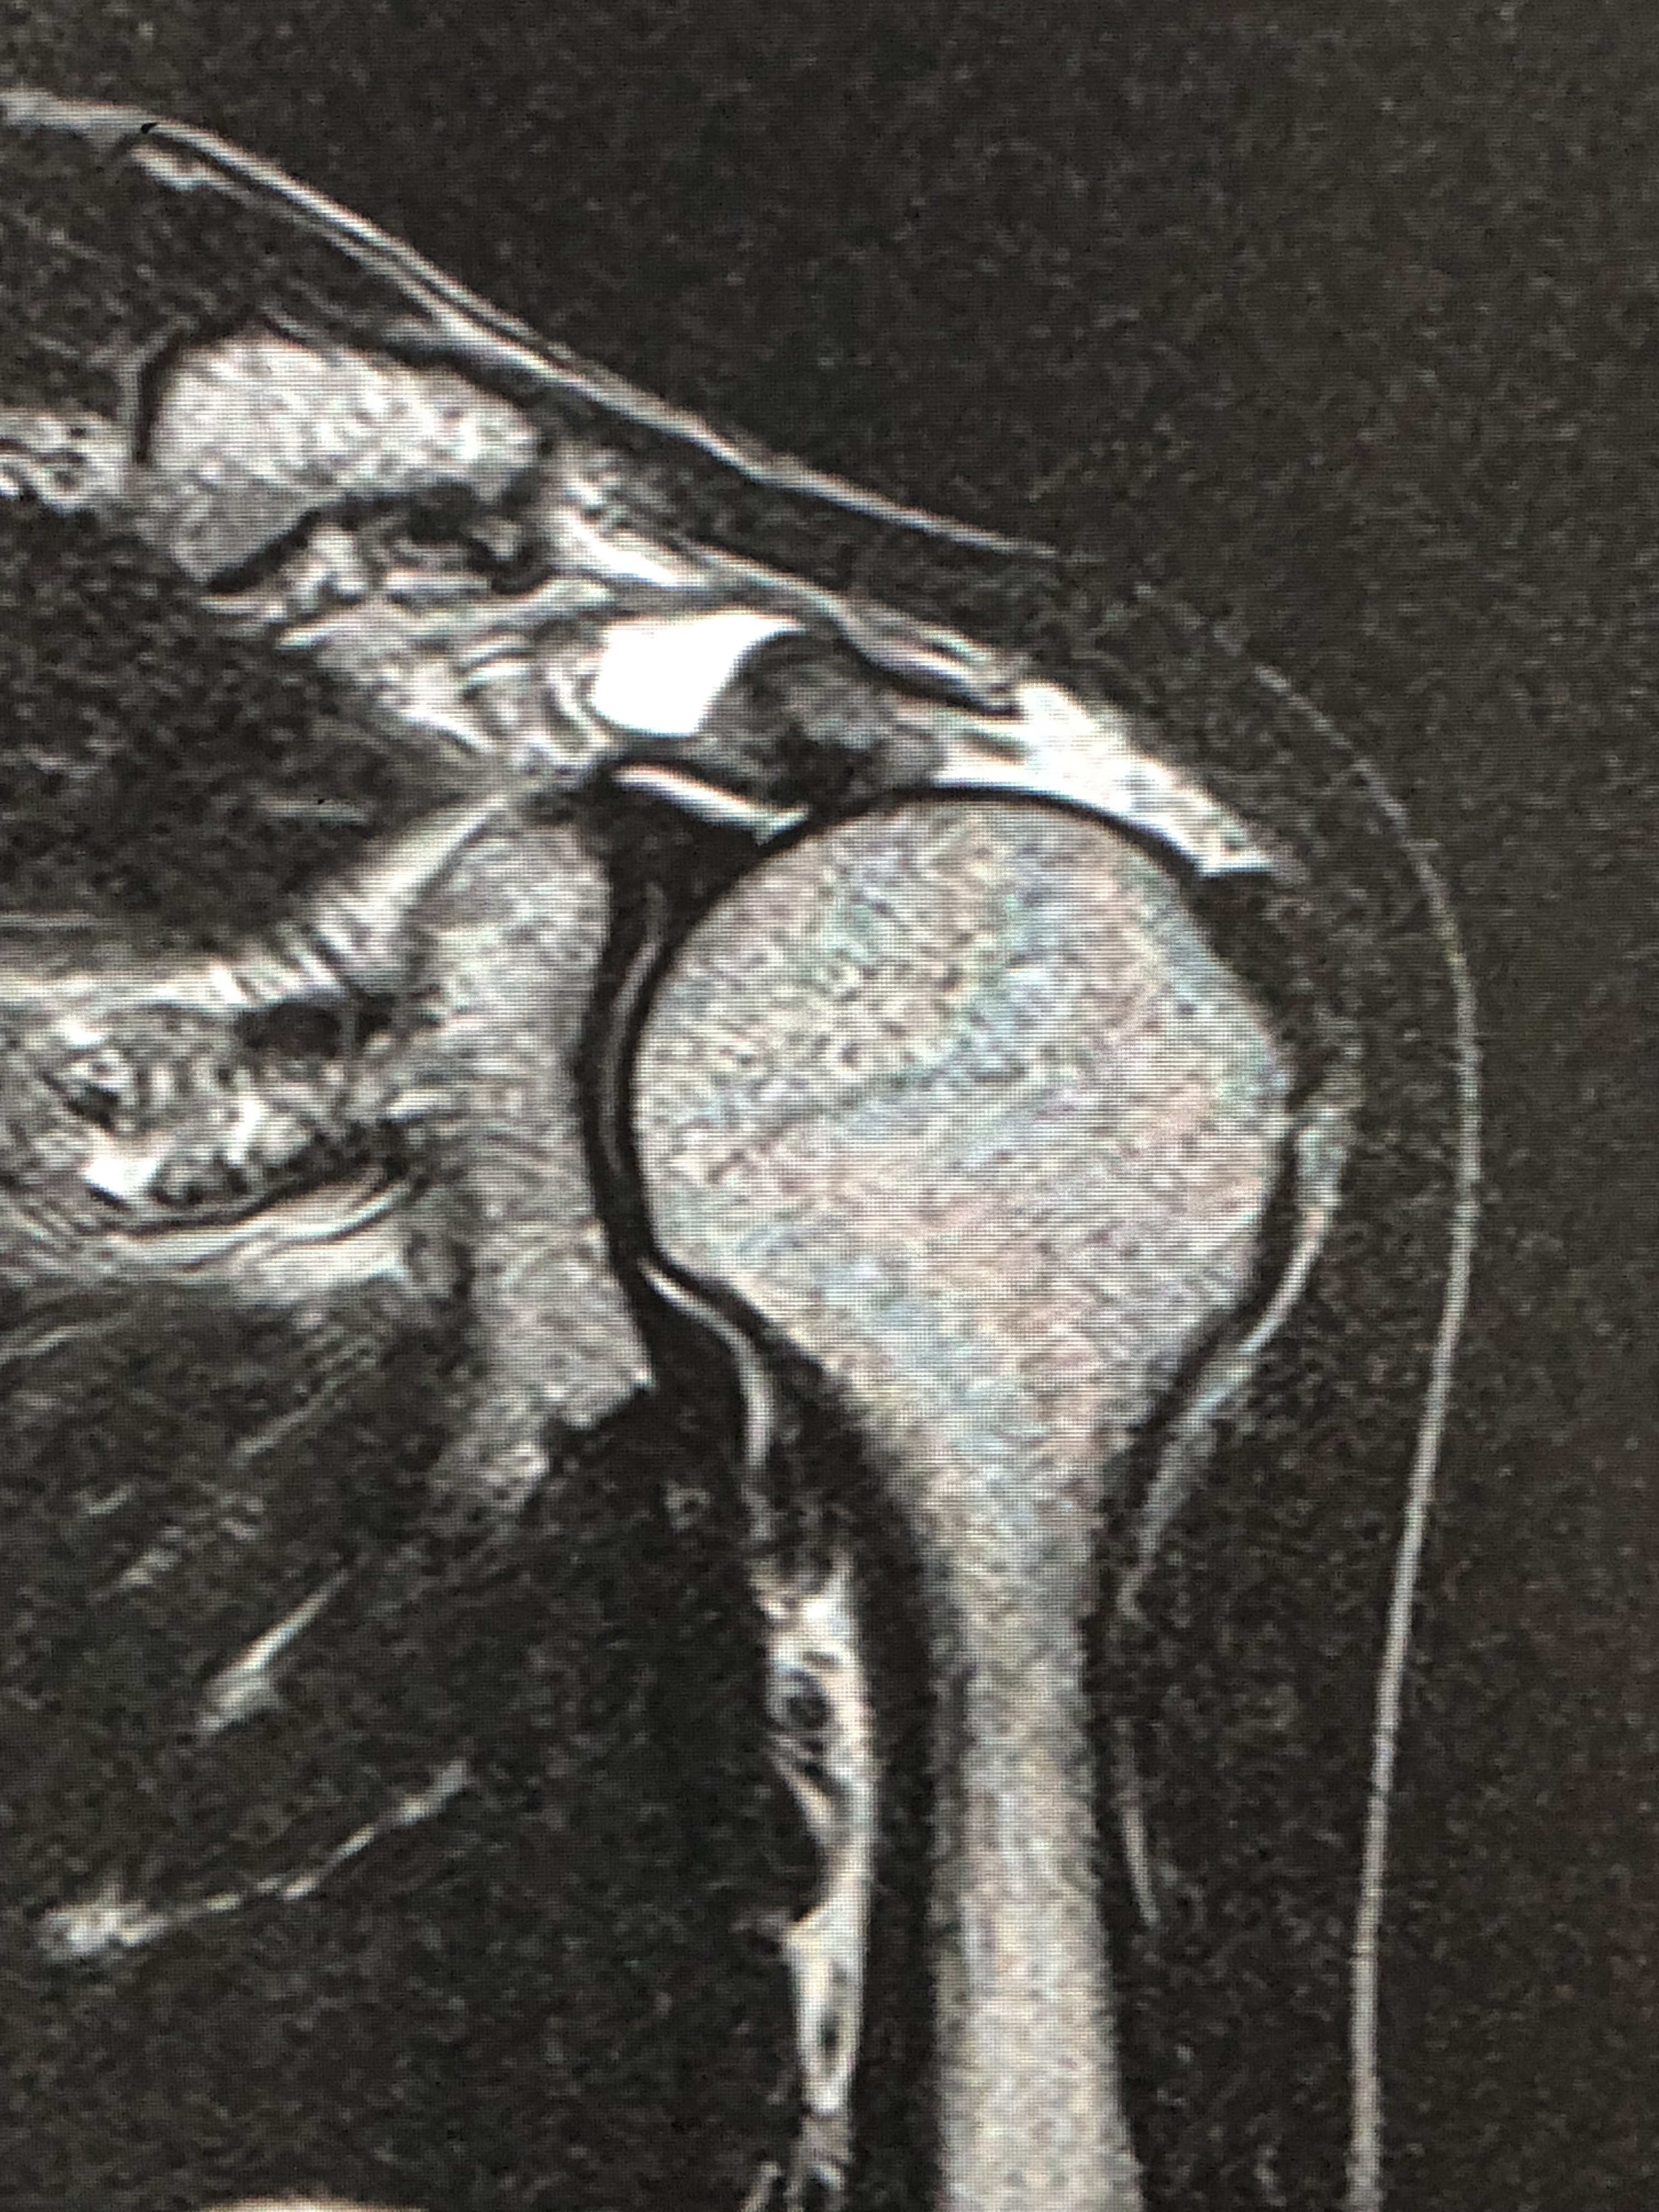

腱板や関節包、関節唇など肩関節の痛みの原因になりやすい部分の多くはMRIが最もよく検出できます。そのため、肩の診察ではMRIでのチェックがオススメです。MRIは緊急時を除くと基本的には予約検査なのでご注意ください。

60歳以上の方で「五十肩だと思うんだけど・・・」ということで受診される患者さんも多いのですが、精密検査をしてみると腱板損傷だったというケースはとても多いです。

さらにレントゲンで骨の変化や関節の変形の有無などをチェックします。例えば、大きな腱板損傷があれば肩峰の下のスペースは狭くなりますし、ときに肩峰の骨棘という骨の出っ張りが出てきます。